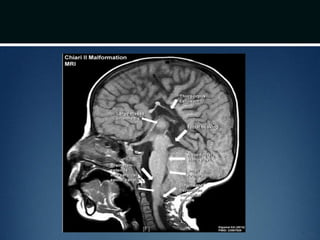

Chiari II malformation

โ€ข Caudal displacement of cerebellar vermis, lower

brainstem and fourth ventricle seen exclusively in

patients with myelomeningocele

โ€ข Numerous other anomalies associated in various

combinations

โ€“ vertical straight sinus

โ€“ large venous lakes in the tentorium

โ€“ fenestrations in falx, which is often not well formed โ€“ gyri

of left and right hemispheres interdigitate โ€“ โ€œChinese

letteringโ€ on axial MRI

Chiari II malformation โ€ขCaudal displacement of cerebellar vermis, lower brainstem and fourth ventricle seen exclusively in patients with myelomeningocele โ€ข Numerous other anomalies associated in various combinations โ€“ vertical straight sinus โ€“ large venous lakes in the tentorium โ€“ fenestrations in falx, which is often not well formed โ€“ gyri of left and right hemispheres interdigitate โ€“ โ€œChinese letteringโ€ on axial MRI